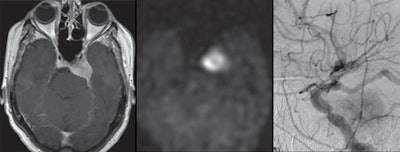

Arterial spin labeling (ASL) MRI could become a viable complement to digital subtraction angiography (DSA) in screening for hypervascular meningiomas and determining the need for presurgical intervention, according to a study published in the November issue of the American Journal of Roentgenology.

If ASL-MRI can detect increased tumor blood flow in meningiomas that have heightened tumor vascularity on DSA -- also known as tumor blush -- clinicians will have a much better handle on which patients might benefit from preoperative embolization.

"We hypothesized that increased ASL signal intensity within meningiomas will correlate with the presence of tumor blush on DSA, suggesting that this imaging modality can reliably identify meningiomas that are hypervascular," the authors wrote.

Based on ASL images, two independent readers detected all 39 meningiomas, which had a mean size of 9.8 (± 12.2) cm2. Meningiomas with tumor blush had a mean size of 13.4 (± 2.4) cm2, compared with a mean size of 2.7 (± 2.4) cm2 for meningiomas with no tumor blush. Using DSA, the readers also were able to discern 26 lesions (67%) with tumor blush and 13 lesions (33%) with no tumor blush.

As one might expect, mean normalized tumor blood flow was significantly higher in the tumor blush group (4.7 ±1.1), compared with the lesions with no tumor blush (1.5 ±1.1) (p < 0.001). When the researchers used the benchmark of 2.7 for normalized tumor blood flow, they achieved sensitivity of 88% and specificity of 67%. However, they declined to endorse the cutoff of 2.7 as "a single threshold for routine use," because of the study's small sample size.